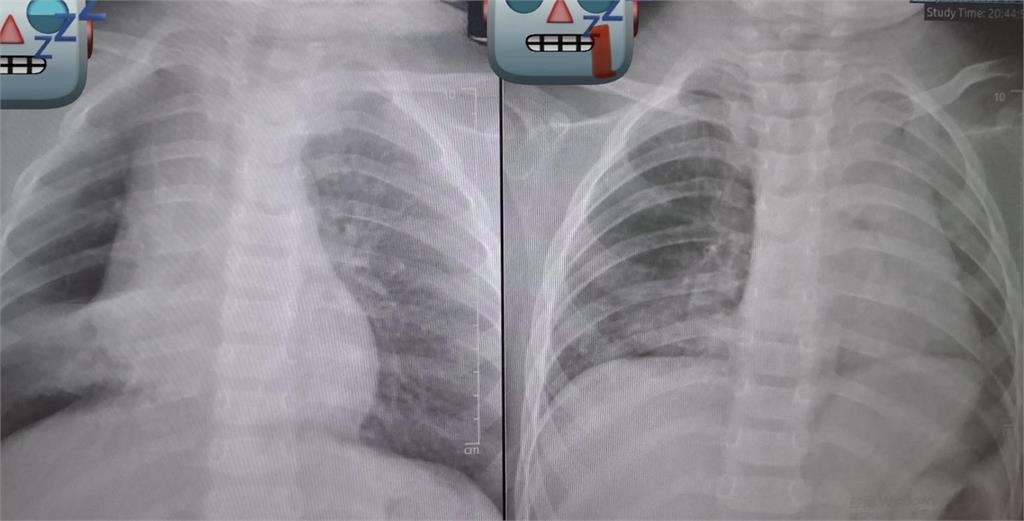

花生卡氣管 3 天長肉芽,追蹤X光後發現孩童的「肺部已經開始塌陷」。(圖/「廖穗綾醫師的健兒門診-Hablo Español」授權提供)

基隆長庚醫院兒科教授級主治醫師廖穗綾今(12日)在臉書粉專發文指出,上週原本要和家人去吃大餐,卻臨時接到一名緊急轉送來的1歲多病童,了解事發經過後,孩子3、4天前阿嬤餵食孫子一整顆花生,接著便開始出現咳嗽與喘鳴聲,雖然剛開始症狀不明顯,但隔天追蹤X光後發現孩童的「肺部已經開始塌陷」,直呼不能輕忽。廖醫師的丈夫賴醫師緊急召集加護病房團隊與資深技術員,準備進行手術。然而手術過程異常艱難,廖穗綾描述,那顆花生已經卡了3天,周圍長出了肉芽,「整顆又大又肥,死死塞住支氣管」,賴醫師表示從來沒有遇到這麼困難的案例,經過長達2個小時的搶救,才把那顆「會跳舞的花生」成功網住、夾出。